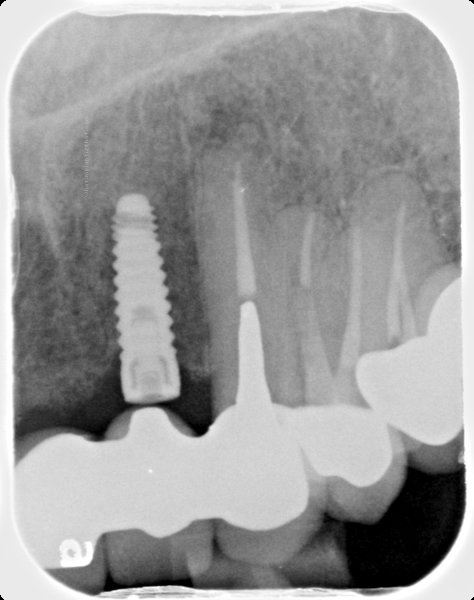

Micro-Vent 2

Connection Interface

Internal interface

Body Shape

Tapered body

Thread Design

ThreadedRounded threads

Straight flangeCurved apexRound hole